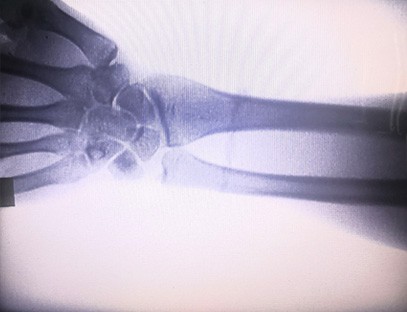

Przenośny aparat rentgenowskijest niskodawkowym, bardzo bezpiecznym przenośnym instrumentem, który może uzyskać wysokiej jakości obrazy przy jednoczesnym zmniejszeniu narażenia na promieniowanie. Kompensuje niedociągnięcia dużego sprzętu szpitalnego i może być przenoszony i transportowany w dowolnym momencie. Szczególnie nadaje się do jednostek i osób o niewystarczającym budżecie i niskich wymaganiach dotyczących obrazów. Nasz aparat rentgenowski nowej generacji jest wyposażony w 10-calowy duży ekran o wysokiej rozdzielczości, który ma większy zakres kąta widzenia i może w pełni zobaczyć całą dłoń, w tym złamania, zwichnięcia, zapalenie stawów i guzy kości. Można go podłączyć do drukarki filmowej w celu drukowania filmów ortopedycznych, a także można go używać do produkcji przemysłowej i testów. Nie ma potrzeby ciemni, bezpośredniej perspektywy, obserwacji w czasie rzeczywistym. Ten aparat ma system obrazowania o wysokiej rozdzielczości, który może bardzo wyraźnie rejestrować obrazy dowolnej struktury kostnej. Aby zapewnić najlepszy sprzęt do badań rentgenowskich i rozwiązania dla producentów wyrobów medycznych, weterynaryjnych, przemysłowych, elektronicznych, działów kontroli i konserwacji oraz laboratoriów badawczych.

Specjalizacja:Zaprojektowany z myślą o potrzebach klinik ortopedycznych, szczególnie odpowiedni dla:Obrazowanie rentgenowskiekończyn takich jak: dłonie, nadgarstki, łokcie, ramiona, kolana, kostki itp.

Wyraźne obrazowanie:Zaawansowana technologia obrazowania cyfrowego jest wykorzystywana do wykonywania wysokiej jakości zdjęć rentgenowskich, pomagając lekarzom w dokładnym diagnozowaniu schorzenia.